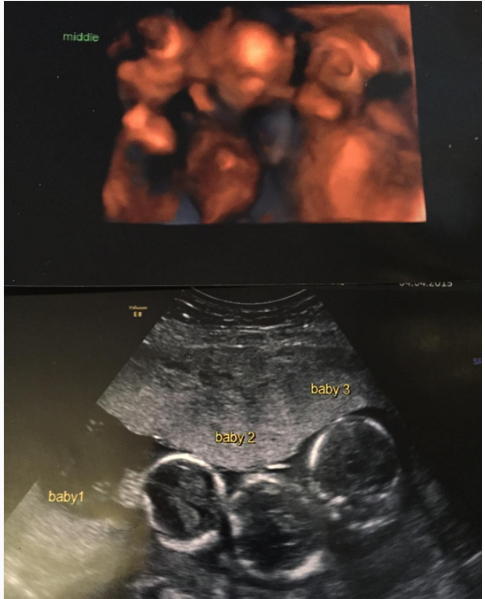

La jeune maman ne cesse d’avoir des nausées sévères suivies des migraines. Elle se rend à l’hôpital pour faire une échographique.Ce que les médecins lui disent la mettra dans un état de choc, mais aussi dans une surprise incroyable.

La bonne nouvelle est que Becki attend des triplés ! C’est tout un choc pour les parents qui commencent à anticiper l’avenir. « Ce fut le plus grand choc de ma vie ! Nous n’avions aucun triplés dans nos familles respectives. »

Heureusemnt, la grossesse se déroule sans complications et les bébés sont en bonne santé. Même si les bébés sont encore minuscules après quelques semaines, le travail et les contractions ne cessent de s’amplifier chez la maman.

Par la suite, les triplés Rocco, Rohan et Romain naissent par césarienne, pesant 1,5 kilo chacun. Les nouveaux nés passent leurs premières semaines aux soins intensif jusqu’à ce qu’ils grandissent.

Toutefois, ils sont bien difficiles à différencier et pour cause, ce sont des triplés monozygotes ! C’est un très rare phénomène devant lequel les médecins sont perplexes vis-à-vis des résultats d’un test d’ADN.